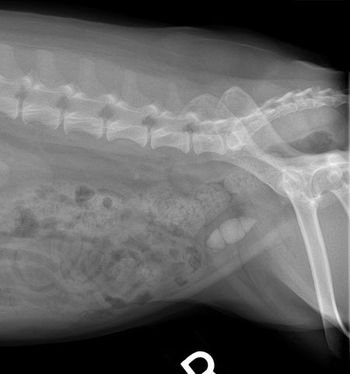

Sick of seeing "stoned" cats and dogs at your veterinary practice? Dont pass the chance to stop the strain by preventing recurring bladder stones in dogs and cats.